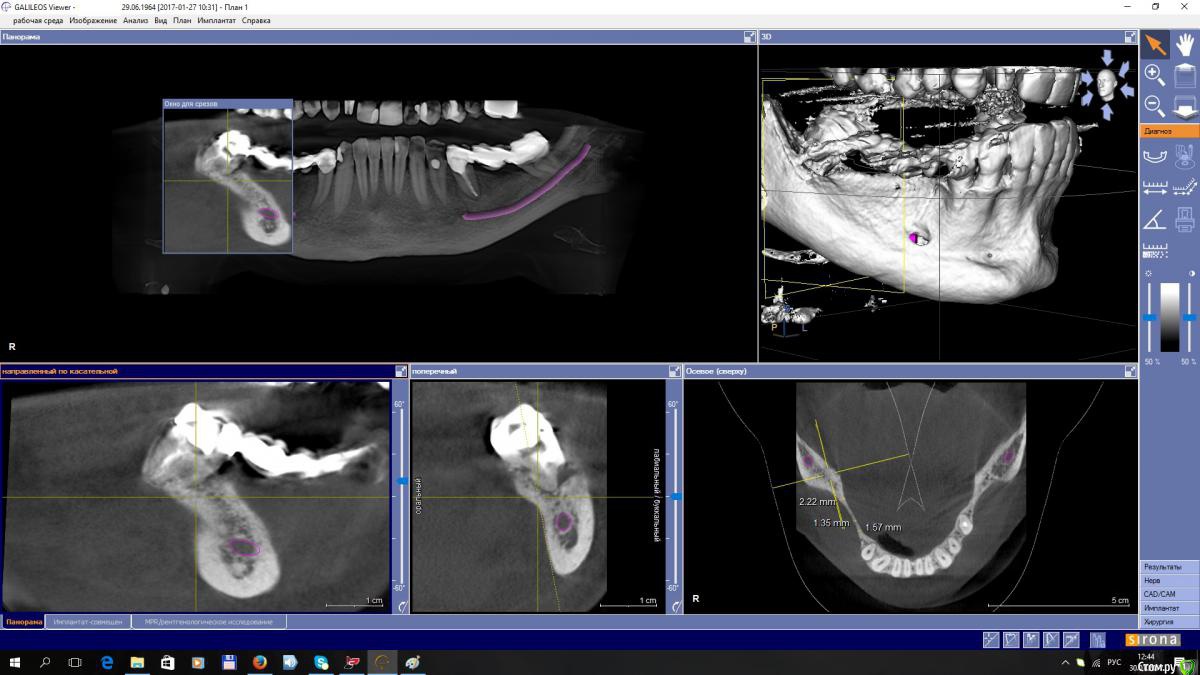

EEcho Опубликовано 27 января, 2017 Поделиться Опубликовано 27 января, 2017 (изменено) Уважаемые коллеги!Прошу совета!? Как увеличить объём, каким методом? Я в затруднении. За ранее большое спасибо! Изменено 27 января, 2017 пользователем EEcho Ссылка на комментарий

gum Опубликовано 27 января, 2017 Поделиться Опубликовано 27 января, 2017 А с язычной поверхности, углубление это дефект кости или сосуд там проходит? Ссылка на комментарий

kamranchick Опубликовано 28 января, 2017 Поделиться Опубликовано 28 января, 2017 Уважаемые коллеги!Прошу совета!? Как увеличить объём, каким методом? Я в затруднении. За ранее большое спасибо!покажите срезы дальше(дистальнее) может целесообразно провести аугментацию дистально, возможно там ситуация получше... и сделать медиальную консоль на 5ый зуб. 1 Ссылка на комментарий

EEcho Опубликовано 30 января, 2017 Автор Поделиться Опубликовано 30 января, 2017 А какими методиками владеете?Наверное всеми ныне существующими. костной пластикой занимаюсь порядка 8-ми лет, но с таким ножевидным гребнем встречаюсь в первые. сплошная кортикалка, кровоснабжение гребня желает быть лучше, есть мысль разрез сделать на 3 мм ниже гребня язычно, без отслойки лоскута с язычной, и мембрану бить в открывшуюся кость. но есть сомнения. не могу прогнозировать отдаленный результат. Ссылка на комментарий

EEcho Опубликовано 30 января, 2017 Автор Поделиться Опубликовано 30 января, 2017 покажите срезы дальше(дистальнее) может целесообразно провести аугментацию дистально, возможно там ситуация получше... и сделать медиальную консоль на 5ый зуб.Срезы в области 45, 46, 47,48, Ссылка на комментарий